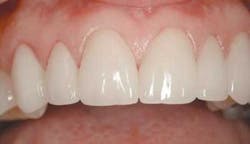

The final result of this case sees an improvement in all of the original objectives (Figs. 12, 13, 14). Our patient wanted a lighter, wider smile that would cover the darkness she had lived with her entire life. Needless to say, she was ecstatic with the end results (Figs. 15, 16).

null